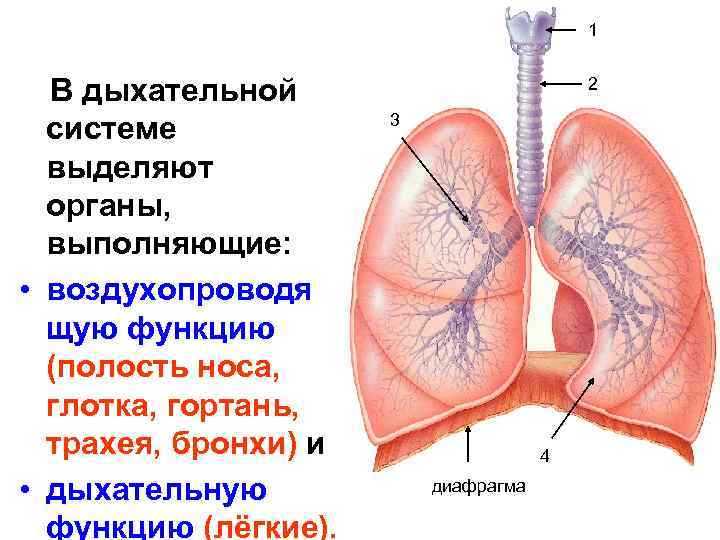

Роль легких в метаболических процессах